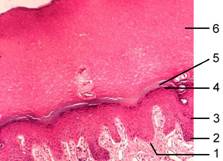

Рис. 5-1А. Эпидермис представлен многослойным плоским

ороговевающим эпителием, расположенным на базальной мембране (1). В

эпидермисе различают несколько слоёв. В базальном слое (2) находятся

цилиндрические клетки. Следующий слой — шиповатый (3) занимают клетки

полигональной формы с многочисленными отростками. Над шиповатым находится

зернистый слой (4), представленный уплощёнными клетками с гранулами кератогиалина.

Далее располагается блестящий слой (5). В клетках этого слоя содержится

светопреломляющее вещество элеидин, поэтому слой выглядит как блестящая

гомогенная полоска. В самом поверхностном — роговом слое (6) эпидермиса

толстым пластом расположены роговые чешуйки, совокупность которых образует на

препарате широкую равномерно окрашенную полосу. Окраска гематоксилином и

эозином.

Рис. 5-2А. Эпидермис представлен многослойным плоским

гомогенная полоска. В самом поверхностном — роговом слое (6)

эпидермиса толстым пластом расположены роговые чешуйки, совокупность которых

образует на препарате широкую равномерно окрашенную полосу. Окраска

гематоксилином и эозином.